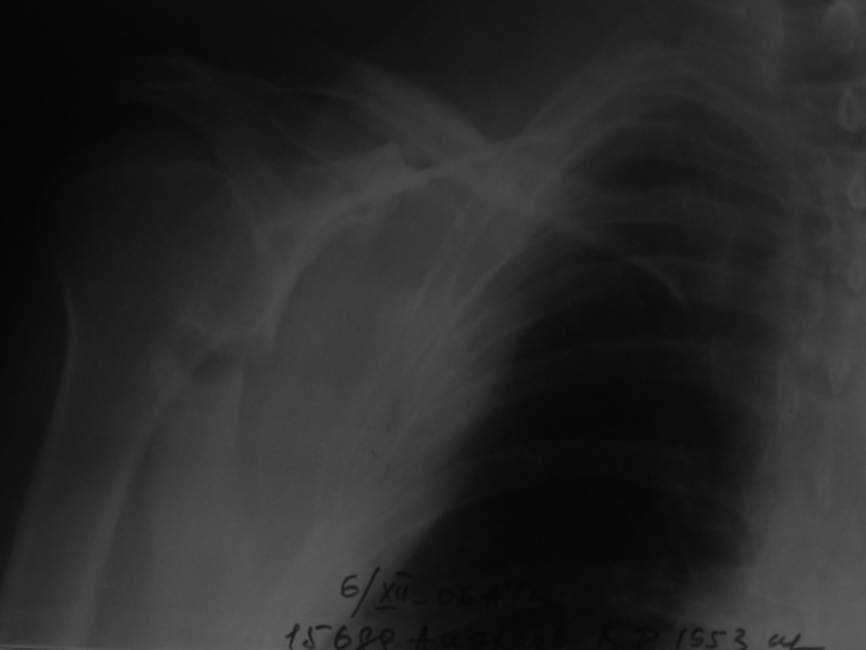

Уважаемые коллеги, помогите определиться с тактикой. Больной 1953гр, травма на стройке, придавило тяжелымпредметом. Сейчас в сознании, стабилен, плевральная полость задренирована. Предполагаем синтез ключицы, если бы не переломы ребер, установили бы шину ЦИТО.Есть у кого опыт открытого/закрытого синтеза подобной лопатки? Что делать с клювовидным отростком? Спасибо, Моисеев Ю.И.